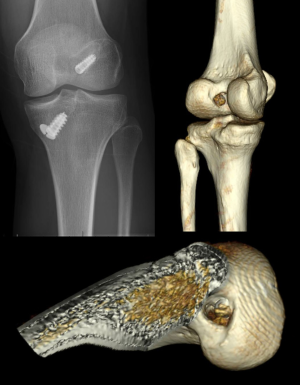

On the other hand, a staged approach with bone grafting remains a viable strategy (Figure 2). Staged procedures have been reported to restore knee laxity measurements similar to that achieved with primary ACL reconstruction, but are associated with worse subjective outcomes. This is likely due in part to secondary meniscal and/or chondral lesions acquired in the interim between bone grafting and revision ACL reconstruction (41,42). However, a recent cohort study comparing one-stage versus two-stage revision ACL reconstruction found no differences between groups in objective and subjective outcomes at 2-year follow-up (43). Nevertheless, presumed equivalence between treatment strategies may be questioned as the one-stage revision group was comprised of patients with bone tunnels completely outside of the native insertion sites, while the two-stage revision group underwent bone grafting as they had enlarged bone tunnels (>16 mm) or those that would critically overlap with anatomic tunnels (43).